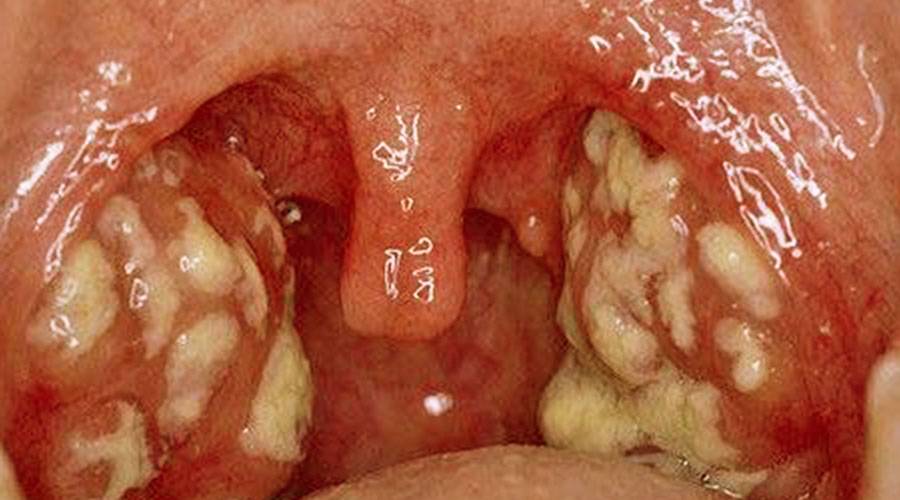

Фолликулярная ангина — характеризуется сильной болью в горле, усиливающейся при глотании, и иногда отдающая в уши. Температура тела может повышаться до 38-40 °С, симптомы интоксикации — головная боль, слабость, озноб, тянущая боль в пояснице. Увеличиваются подчелюстные лимфатические узлы, на нёбе и миндалинах видны маленькие бело-желтые точки.

Лакунарная ангина у взрослых — протекает тяжелее, чем фолликулярная. Общие симптомы ангины такие же, только значительно выраженные. Нёбо приобретает ярко-красный цвет, на миндалинах отмечается налёт жёлтого цвета. В редких случаях температура поднимается до 40° С.

Фиброзная ангина — является осложненным случаем двух предыдущих вариантов. Для ней характерен единый сплошной налёт бело-желтого цвета, который может выходить за пределы миндалин.

Налет на миндалинах при ангине.

- Увеличиваются, отекают, краснеют небные миндалины. При бактериальной форме заболевания на них могут быть язвы, серозный или гнойный налет. При герпетической ангине гланды покрываются характерными пузырьками с серозным содержанием. При кандидозной ангине налет на гландах белый.

- На гландах образуются гнойные пробки.